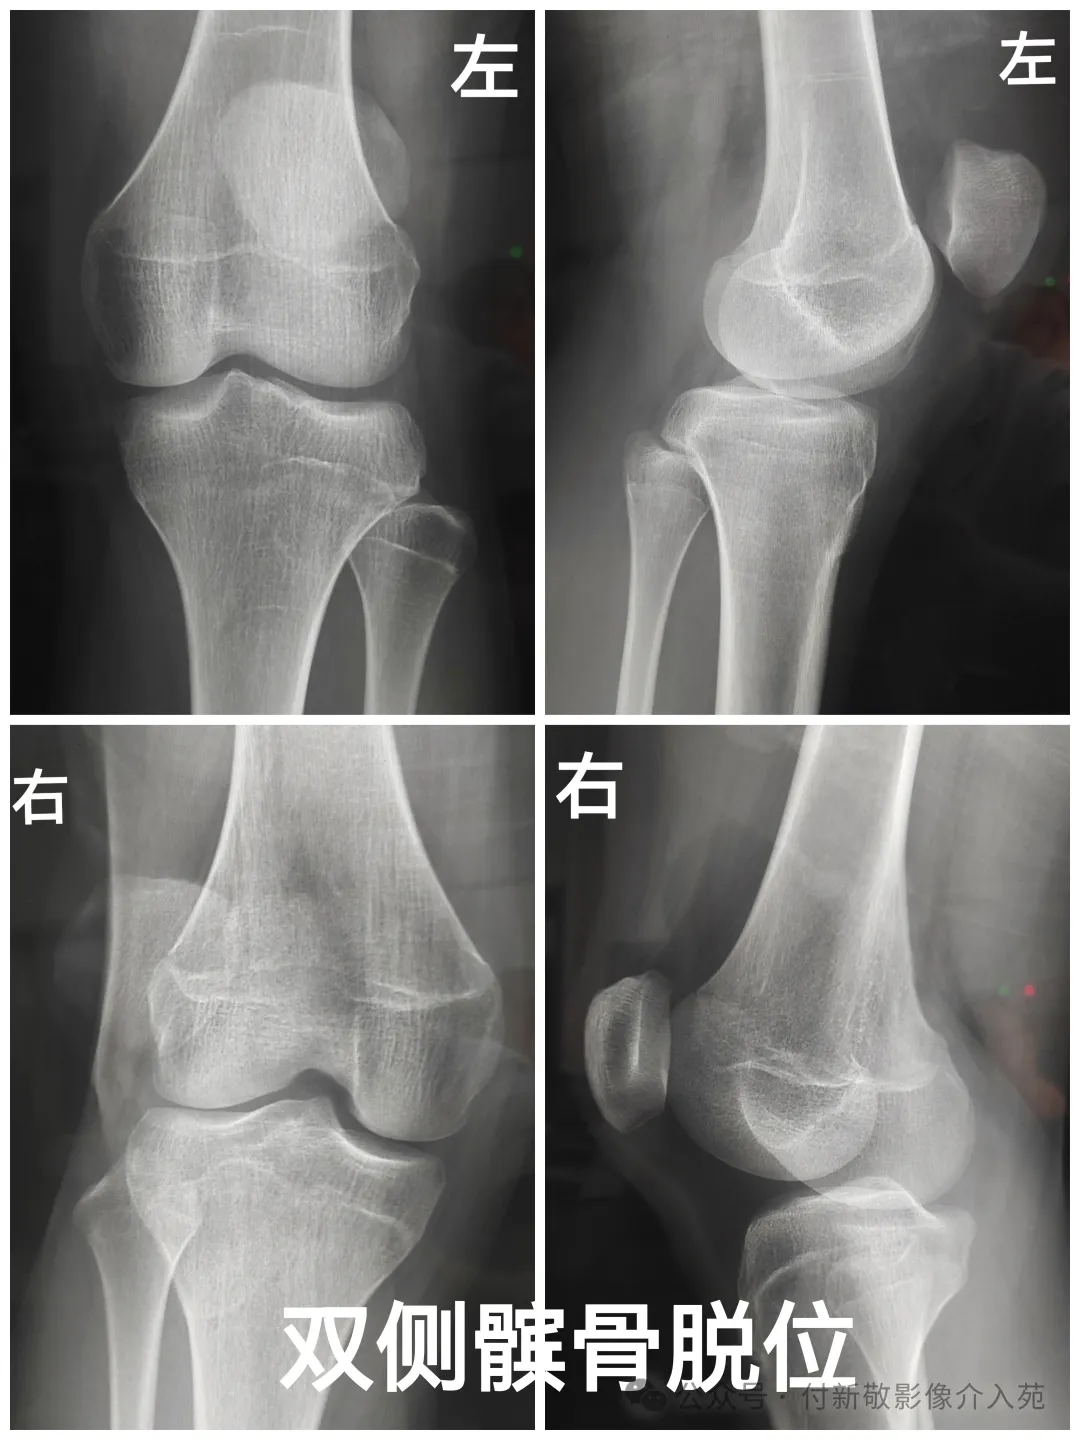

十一、髌骨脱位

髌骨脱位:髌股关节在运动过程中,髌骨的关节面与股骨滑车关节面移位,继而导致两关节面部分或者完全失去接触。临床中较常见,绝大多数为外侧脱位。病因包括急性创伤、先天发育异常。常表现为膝关节疼痛、髌骨移位、膝关节无法完全伸直或弯曲等。单纯的急性髌骨脱位可手法复位,合并韧带、关节损伤或反复髌骨脱位的患者,需要手术治疗。

影像学检查:膝关节正侧位及髌骨轴位X线、CT、核磁共振;能显示髌骨内侧面的撕脱骨折和髌股关节位置异常,了解髌骨及滑车发育不良,髌股关节面不相适应及髌骨移位情况。MRI可显示关节内血肿、髌骨内侧面和股骨外髁骨髓水肿,髌骨内侧面骨软骨损伤,及周围韧带损伤的情况。 13.webp